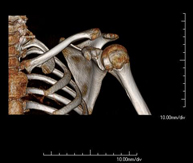

- TC Hombro

Exploración radiológica que mediante un sistema de rayos X y detectores que giran alrededor del paciente, reconstruyendo las imágenes por ordenador (TC Multidetector), permite el estudio de huesos, músculos y articulaciones del hombro.